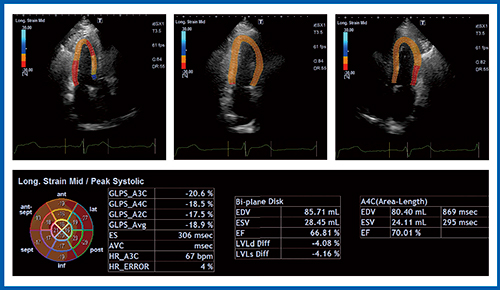

Aplio i900では,biplane disk summation法で左室容積計測を行うと,EFなどに加えてglobal longitudinal strain(GLS)が表示される(図2□:症例1)。GLSを算出する従来の手法である2D Wall Motion Tracking(WMT)(図3 b,図4)では,心内膜のラインを細かく等分し,それぞれの点の長さの変化の合計でストレインを算出する。一方,biplane disk summation法(Auto EF計測)によるGLS(図3 a)は,心内膜のトレースラインの長さの変化をストレインとして算出している。そして,4 chamber viewと2 chamber view双方の平均値から左室GLSが算出される。

症例1について,上記の2つの手法で求めたGLSの値を比較すると,いずれも18.9%であった(図5)。いずれの方法でもかなり近似した値が算出されるが,本症例は壁運動異常がないことに注意する必要がある。

図2 Biplane disk summation法によるGLSの算出(症例1)

図5 Biplane disk summation法と2D WMTによるGLSの比較